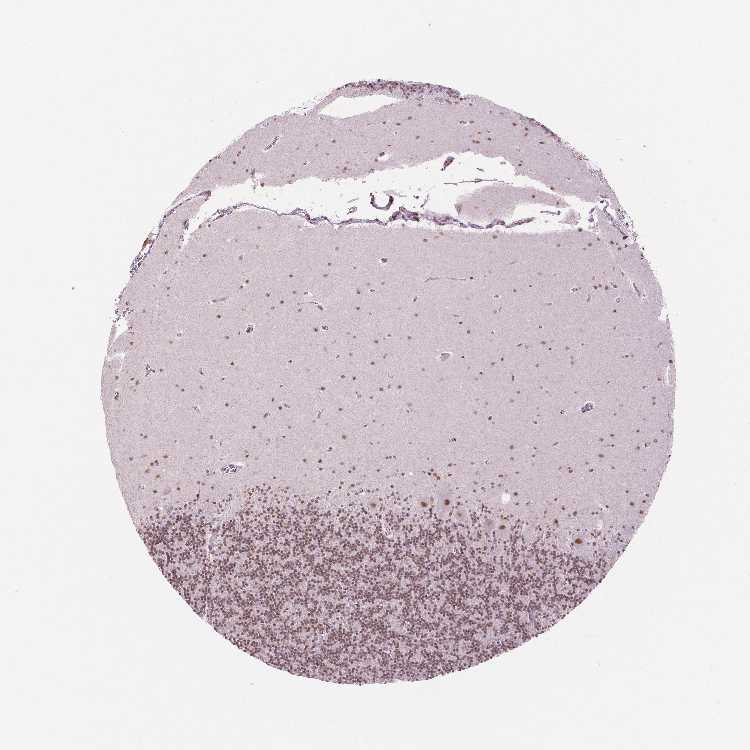

BRAIN CEREBELLUM Show tissue menu

CEREBELLUM - Antibody stainingi

Antibody staining in the annotated cell types in the current human tissue is reported as not detected, low, medium, or high, based on conventional immunohistochemistry profiling in selected tissues. This score is based on the combination of the staining intensity and fraction of stained cells.

Each image is clickable and will lead to virtual microscopy that enables deeper exploration of all samples and also displays staining intensity scores, fraction scores and subcellular localization as well as patient and tissue information for each sample.

Antibody HPA015055Antibody HPA061646Antibody CAB068177Antibody CAB068178

Purkinje cells -HighMediumMedium

Purkinje cells - cytoplasm/membrane High---

Purkinje cells - dendrites High---

Purkinje cells - nucleus Not detected---

Cells in granular layer -HighMediumMedium

Cells in molecular layer -HighMediumHigh

Granular cells - cytoplasm/membrane Low---

Granular cells - nucleus Not detected---

Molecular layer - neuropil Not detected---

Molecular layer cells - cytoplasm/membrane Not detected---

Molecular layer cells - nucleus Not detected---

Processes in granular layer High---

Processes in molecular layer Not detected---

Processes in white matter Not detected---

Synaptic glomeruli - capsule Not detected---

Synaptic glomeruli - core Medium---

White matter cells - cytoplasm/membrane Low---

White matter cells - nucleus Not detected---